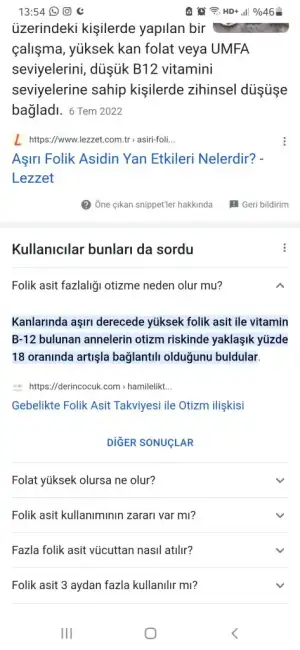

Merhaba ben ebe ve doktordan fazlası zararlı diye duydum bence bırakın kenarda kalsın bebeğe bir zararı olmasın. Benim de marka değiştirdi doktorum önceki folik asiti yeni almıştım gidip asm de ebeye verdim yeni gebe olan olur, alamayan olur bir faydası olmuş olsun diye sizde öyle yapabilirsiniz. Ayrıca folik asit yıllarca içilecek biley değil neden içiyorsunuz bir nedeni mi var

gebe kalmadan önce başlanıyor ya , 2021 mart ayından beri uğraştığımız için hergün alıyorum